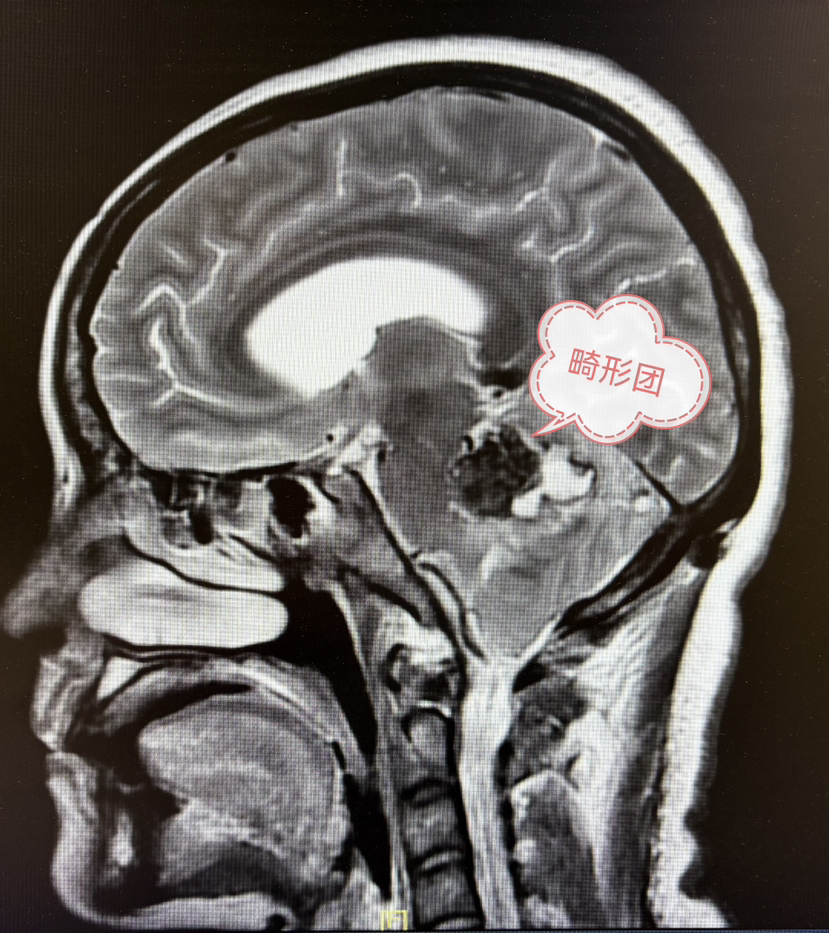

2期术前MRI